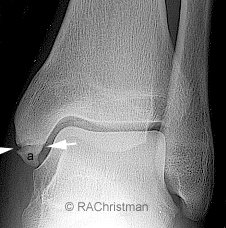

Avulsion Fractures

Imagine you're five, your bones are soft because they haven't hardened yet, but you've got nice strong ligaments. You roll your ankle, badly, and something has got to give. In an adult it's usually the ligament, a sprain will swell up bad and hurt for a bit but the bone won't break. In children, because the bone is soft, the ligament often pulls part of the bone with it. We call this an avulsion fracture. The image below is a beautiful little example!

Image source